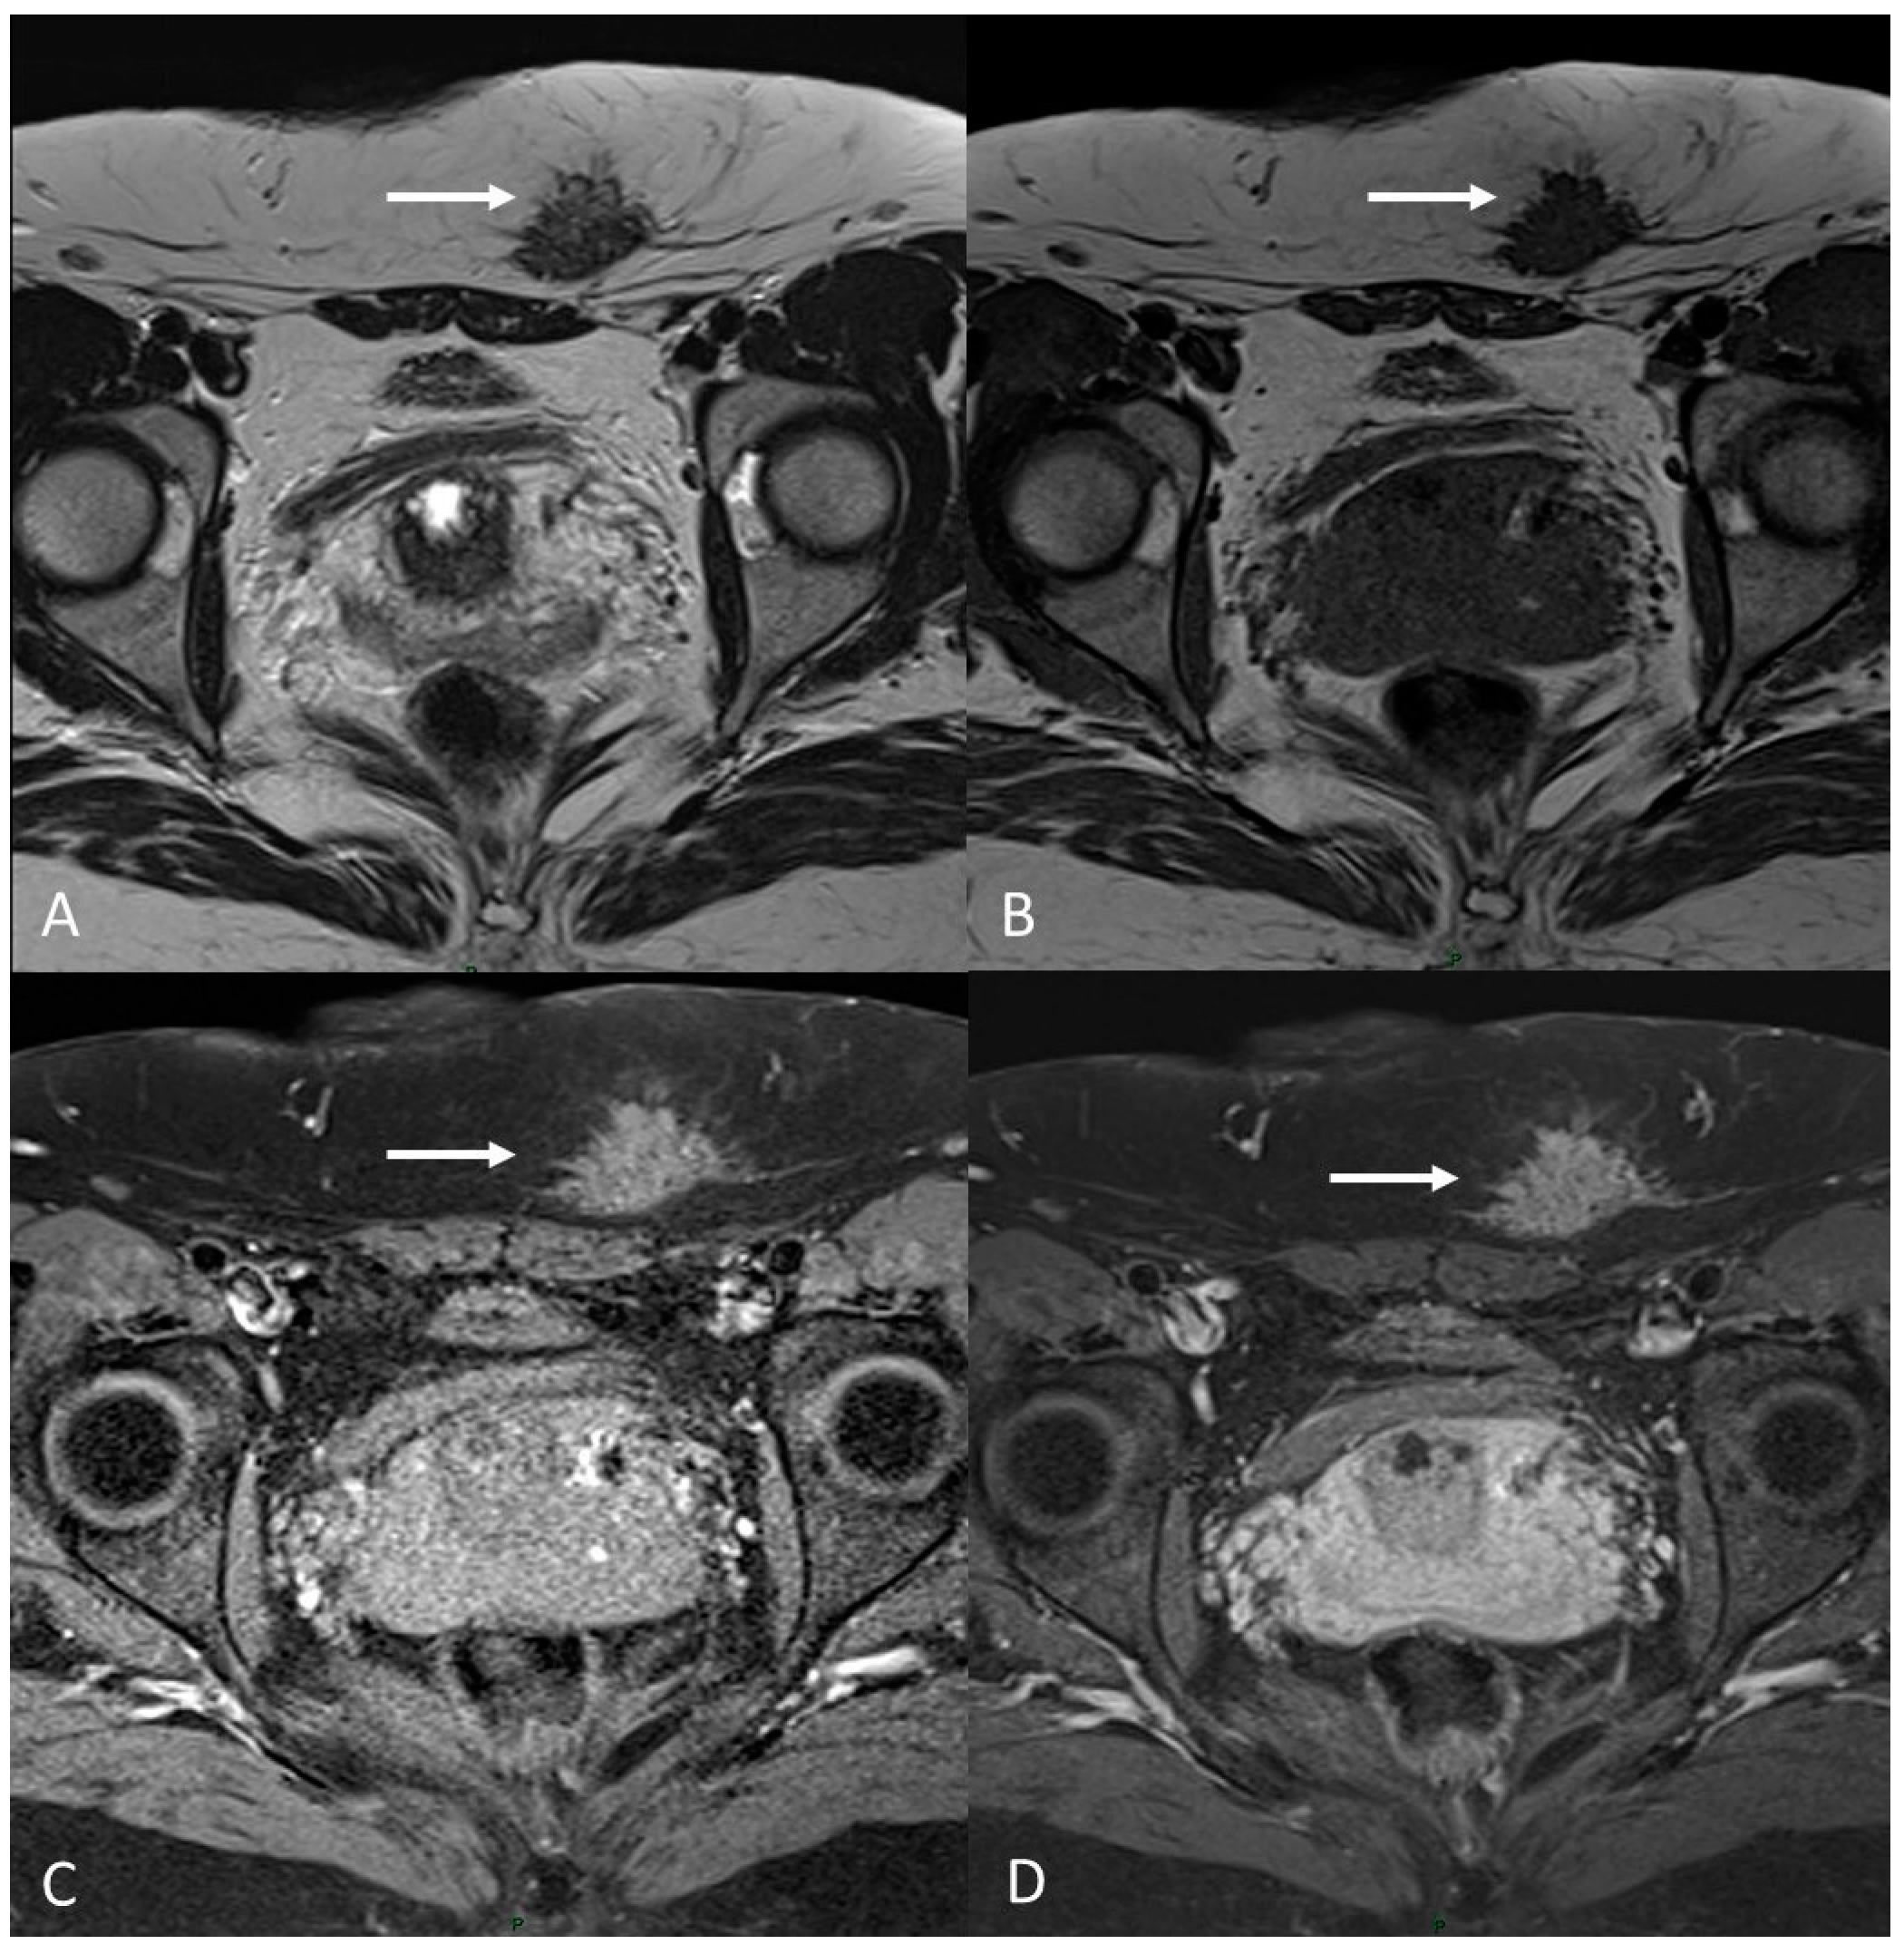

6.1. Soft Tissues Localization

- Andres, M.P.; Arcoverde, F.V.L.; Souza, C.C.C.; Fernandes, L.F.C.; Abrão, M.S.; Kho, R.M. Extrapelvic Endometriosis: A Systematic Review. J. Minim. Invasive Gynecol. 2020, 27, 373–389. [Google Scholar] [CrossRef]

- Chamié, L.P.; Ribeiro, D.M.F.R.; Tiferes, D.A.; de Macedo Neto, A.C.; Serafini, P.C. Atypical Sites of Deeply Infiltrative Endometriosis: Clinical Characteristics and Imaging Findings. Radiographics 2018, 38, 309–328. [Google Scholar] [CrossRef]

| Extra pelvic endometriosis | Abdominal wall | Hypointense solid mass on T2WI with/Without hyperintense hemorrhagic cyst on T1WI | |